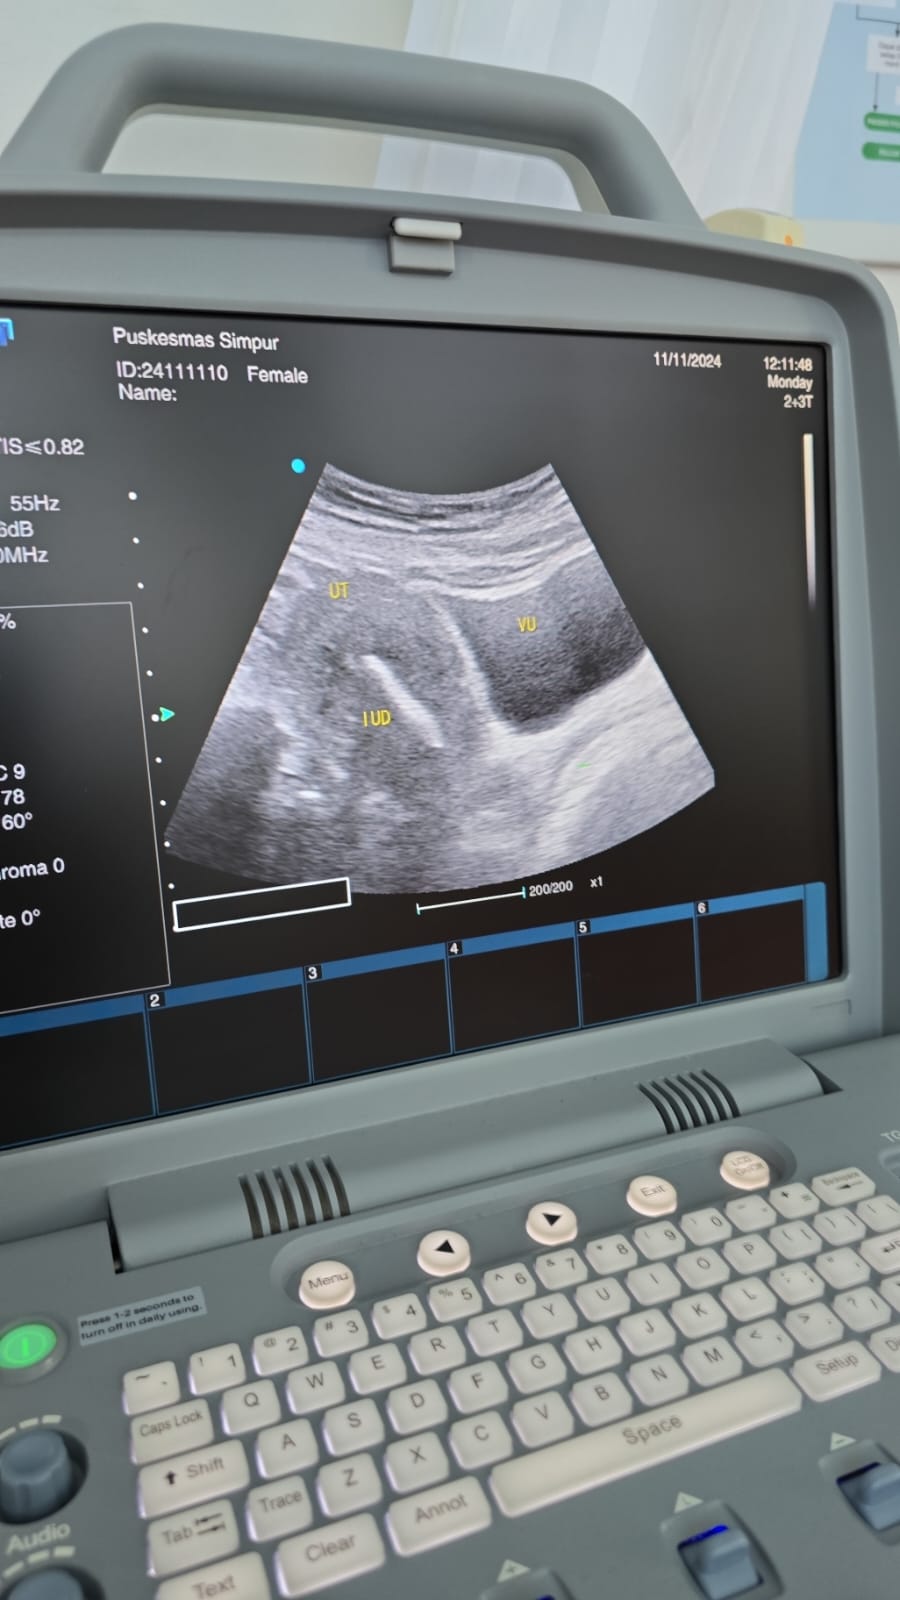

Sebagai salah satu upaya peningkatan pelayanan di puskesmas bagi ibu hamil perlu dilakukan pemeriksaan dengan mengunakan USG (Ultarasonografi) yang bermanfaat untuk mengetahui kondisi kesehatan bayi dan ibu hamil,seperti lokasi kehamilan,jumlah janin dan detak jantung janin. pendampingan ini juga merupakan upaya peningkatan SDM Kesehatan terutama bagi dokter di puskesmas yang langsung dapat pendampingan dari dokter spesialis kandungan RSUD H.Hasan Basry Kandangan ( dr.Eddy Wardhana,Sp.OG). Kegiatan ini dilaksanakan di Puskesmas Sungai Raya,dengan peralatan USG 1 unit punya Puskesmas Sungai Raya dan satu unit punya Puskesmas Simpur dengan peserta ;